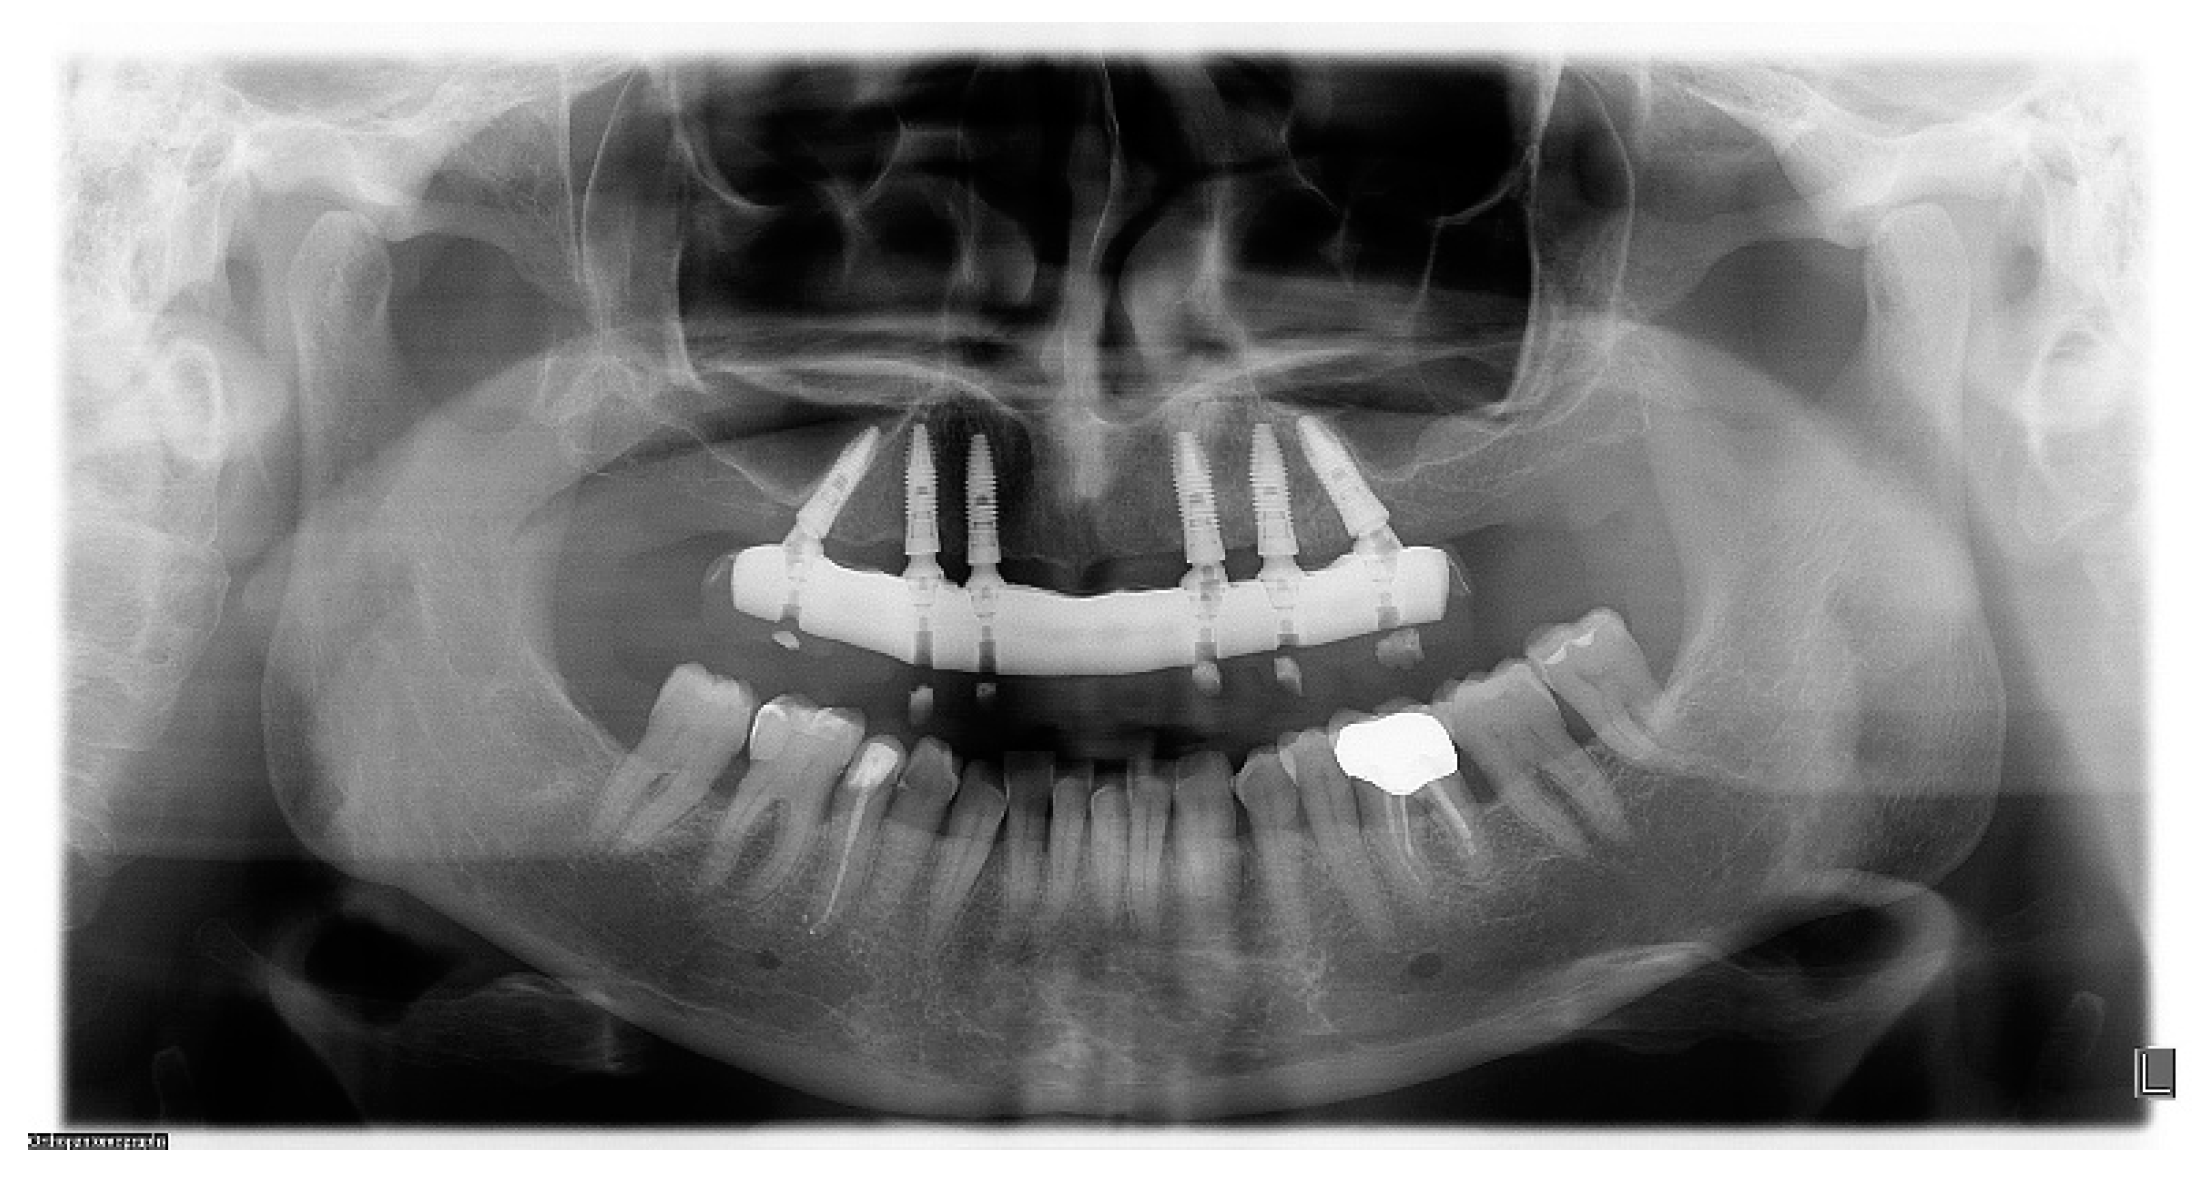

2.7. Radiographic Examination

3. Results

| Bone Loss | IMPLANTS | |

|---|---|---|

| CIG | DIG | |

| 6 months (mm) | 1.03 ± 0.32 | 0.99 ± 0.48 |

| 12 months (mm) | 1.04 ± 0.56 | 1.08 ± 0.52 |

| 24 months (mm) | 1.07 ± 0.66 | 1.11 ± 0.54 |